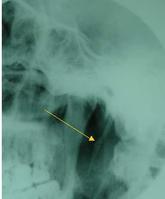

查體:觸診扁桃體區可捫到堅硬條索狀或刺狀突起,患者可訴此處為不適之處,並可誘致咽痛或咽痛加重。多為單側過長。莖突X線片常顯示其長度過長,或有偏斜、彎曲等情況。

3 .螺鏇CT和三維(3D)重建技術:行螺鏇CT橫斷位、冠狀位掃描及3D重建。CT專家認為,在X線平片斷層顯示莖突或莖突舌骨韌帶骨化欠佳時,應選擇CT冠狀位掃描及3D重建。眾所周知,CT的密度解析度遠遠大於X線平片,CT對莖突舌骨韌帶的部分或全部骨化及輕度鈣化顯示較佳。